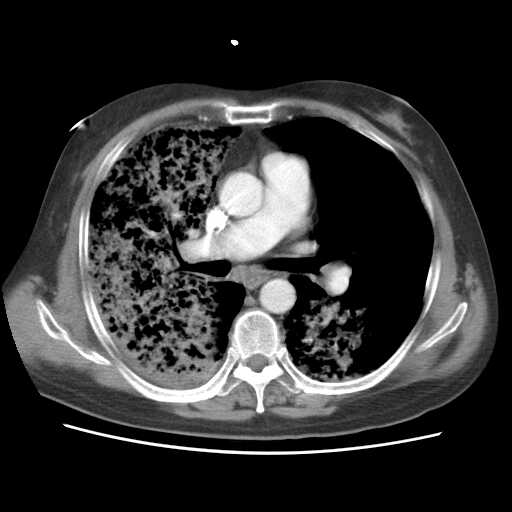

2008.8.17ct

病变从8.11-8.17明显改变,增多,以蜂窝状改变为主,类蜂窝肺,似弥漫性肺泡癌,但是病变进展太快,不符合弥漫性细支气管肺泡癌。因此考虑为特殊微生物感染,多以霉菌类常见,建议细菌微生物学检查。

1.肺动脉梗塞,增强cta肺动脉各级分支未见充盈缺损征象.

疑点二:影象表现怪异,大片阴影内见多发筛孔征,如何解释.

间质为主,血管炎性水肿?

结合临床慢支炎肺气肿,肺心病病史,三次胸片观察可见病情发展变化迅速,病情凶险,考虑多重感染伴ards.